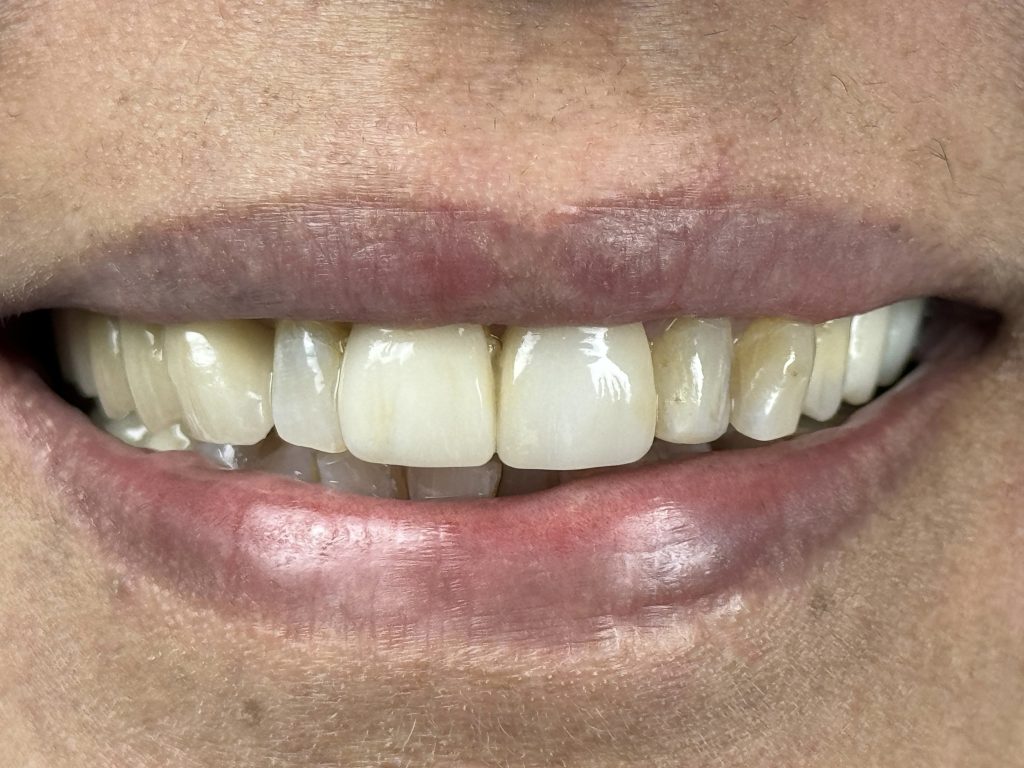

PROSTHETIC REHABILITATION

Monolithic zirconia crowns were selected due to:

- Superior fracture toughness

- Resistance to high occlusal loads

- Minimal wear to opposing dentition

- Long-term colour stability

Cementation was performed using dual-cure resin cement under isolation. Occlusion was refined to restore canine guidance and posterior stability.

FIVE-YEAR FOLLOW-UP

At 5 years:

- Tooth structure remained intact

- Prosthetic margins were stable

- Periapical radiographic healing was evident

- Patient remained asymptomatic

- Excellent gingival response observed

- No secondary caries or debonding

- Occlusion stable and functional

✅ Long-term quadrant stability achieved